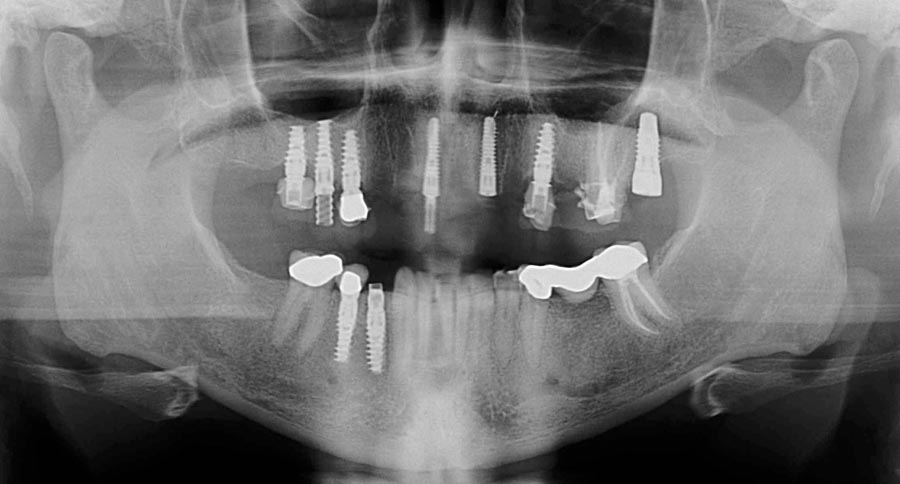

Smile GalleryImplant RestorationsFull Mouth Implant Restoration Full arch zirconia implant bridge (full smile) 1 of 37 Pre-op full smile Pre-op lips retracted Pre-op panoramic x-ray Extraction of strategic teeth Placement of implants Extraction of some remaining teeth after verification of adequate implant stability Occlusal view Post-op panoramic x-ray Immediately fabricated provisional restoration (tissue side view) Immediately fabricated provisional restoration (occlusal side view) Immediate provisional delivered on day of surgery Immediate provisional 2 weeks later Scalloped tissue developed from the provisional at 2 weeks Jig used for making a master impression Provisional in place (full smile) Provisional in place (lips retracted) Provisional in place (right side) Provisional in place (left side) Wax try-in (full smile) Wax try-in (right side full smile) Wax try-in (left side full smile) Wax try-in (full face, lips together) Wax try-in (full smile) Wax try-in (right side) Wax try-in (left side) Wax try-in (lips retracted) Full arch zirconia implant bridge on master cast (frontal view) Full arch zirconia implant bridge on master cast (occlusal view) Implant positions and soft tissue representation on master cast (occlusal view) Soft tissue representation on master cast (frontal view) Full arch zirconia implant bridge (tissue side view) Soft tissues on day of delivery (occlusal view) Soft tissues on day of delivery (frontal view) Full arch zirconia implant bridge delivered (lips retracted) Full arch zirconia implant bridge (lips retracted, close up) Post treatment panoramic x-ray Full arch zirconia implant bridge (full smile)